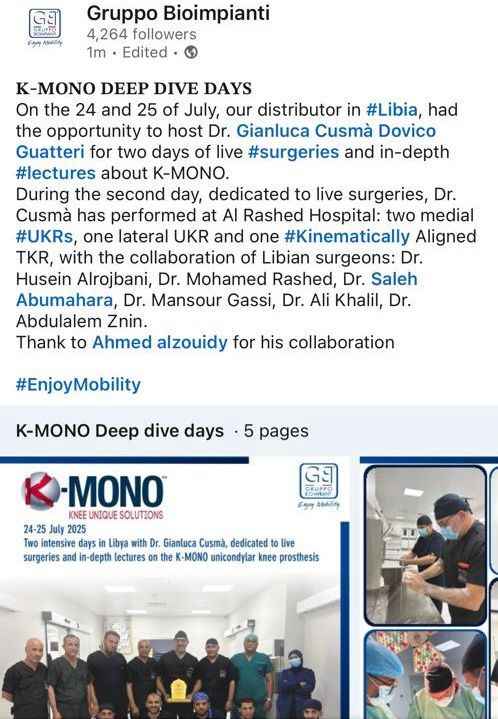

This surgical procedure aims to replace only the damaged portion of the knee joint while preserving the healthy parts, and is used to treat unicompartmental knee osteoarthritis confined to a single compartment.